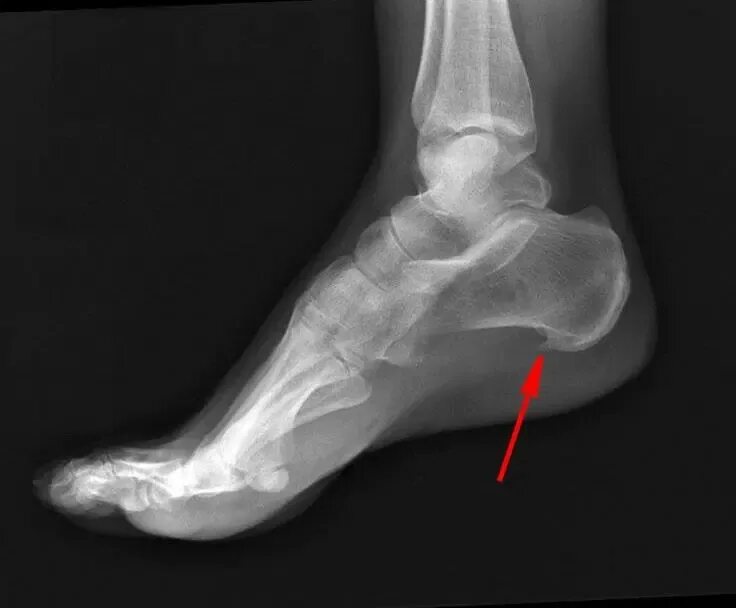

Как называется пяточная шпора